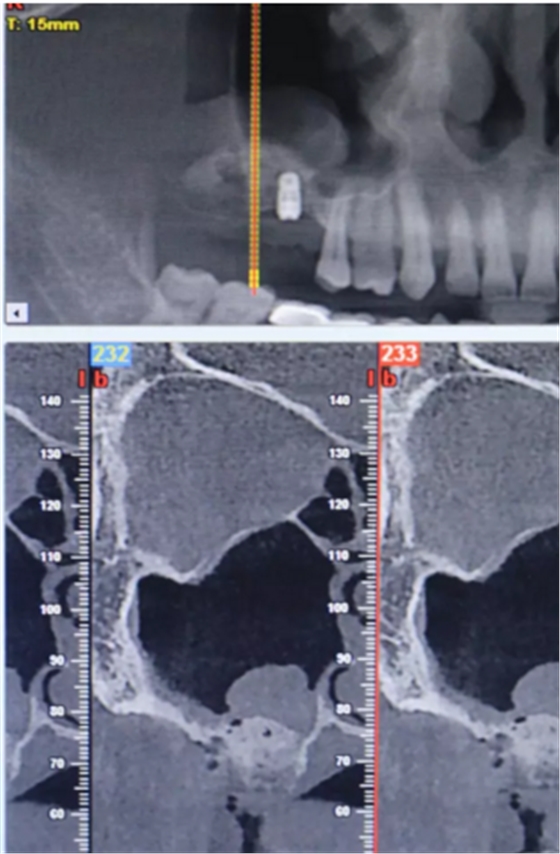

【病例分享】上頜竇大囊腫外提升